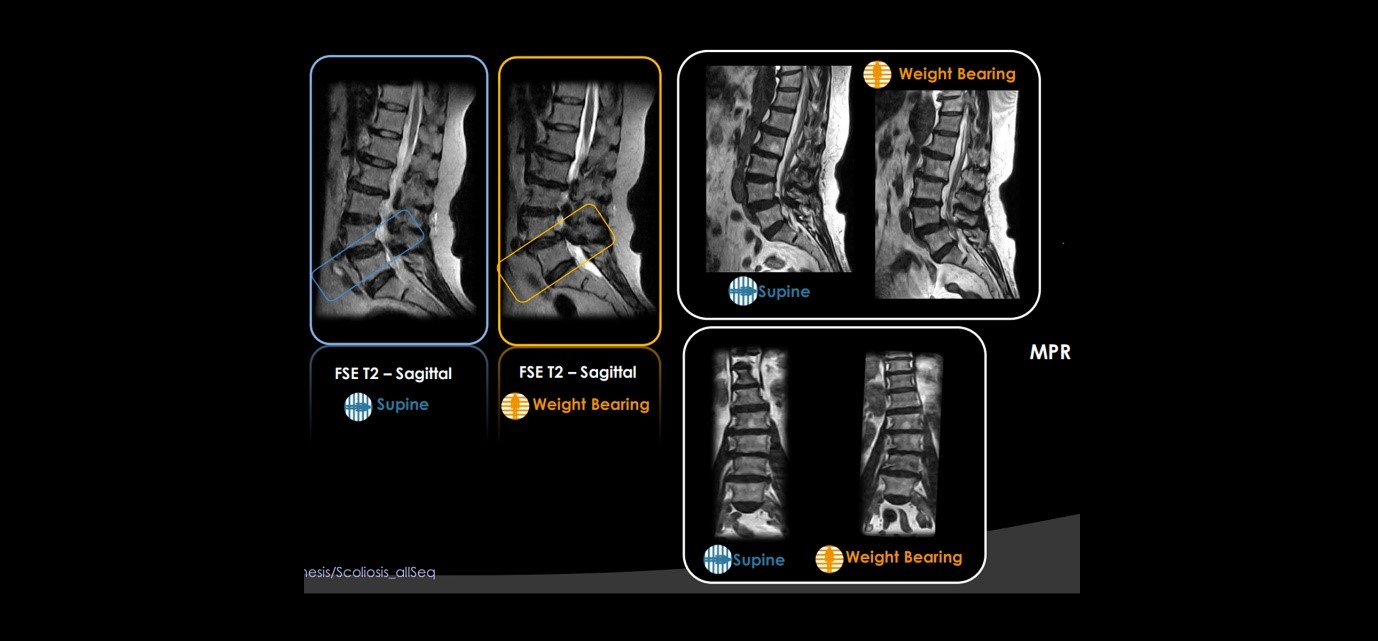

Many symptoms and pathologies occur or are emphasized when the patient is in the weight-bearing position. ESAOTE captures accurate diagnosis for the spine, joints, and MSK conditions. - Reproducing the right biomechanics of several joints and anatomies.

Traditional MRI exams are usually performed in supine positioning with the patient lying down on the scanner bed. However, this position does not reproduce the actual biomechanics of several joints and anatomies like knee, ankle, and spinal columns which are subjected to weight-bearing stress when we are walking or simply standing up.

In our center, Weight-bearing MRI is done to reproduce and study these joints in orthostatic position and find underlying pathologies that are difficult be assess with the conventional supine MRI.